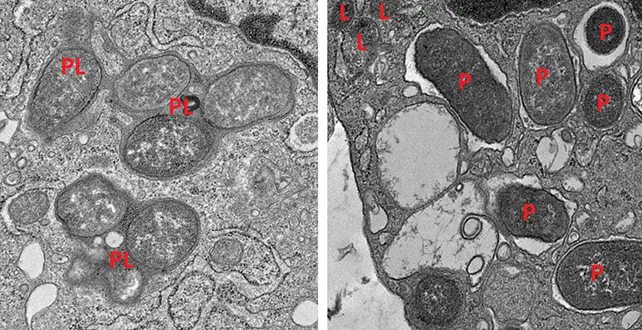

با پیگیری رفتار سلولهای ایمنی بهنام ماکروفاژها از طریق بیان ژنهایشان، پژوهشگران تشخیص دادند کدام سلولها به حفظ سلامت روده کمک میکنند و کدامها به حالت التهابی تبدیل شده و به آسیب میرسانند.

ماکروفاژهای روده میتوانند بین دو حالت تغییر کنند؛ حالت اول برای مبارزه با عفونت (التهابی) و حالت دوم برای ترمیم آسیب (غیرالتهابی). این موضوع بهخوبی ثابت شده است که حفظ تعادل این دو حالت برای یک روده سالم اهمیت دارد.

یک ژن که بهتقویت حالت ماکروفاژ غیرالتهابی کمک میکند، پروتئینی به نام girdin تولید میکند. مشخص شد که پروتئینهای girdin و NOD2 با یکدیگر همکاری میکنند تا ماکروفاژها به تهدیدها هوشیار بمانند اما واکنش بیش از حد نشان ندهند. بدون این دو، ماکروفاژهای در حالت ترمیم کارایی کمتری در پاکسازی اهداف دارند، در حالی که ماکروفاژهای در حالت حمله بهطور افراطی التهابی میشوند.